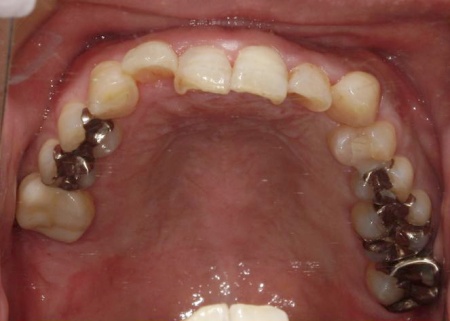

・矯正治療

前歯の反対咬合については、部分矯正で改善を図ります。

前歯の噛み合わせ治療では、上顎の内側に歯を内側から動かす装置「リンガルアーチ」を装着します。併せて、上前歯の表面に「ブラケット」と呼ばれるボタン状の装置を接着し、そこにワイヤーを通して歯を動かす「マルチブラケット装置」を用いて部分矯正を行いました。

最後に、噛み合わせが改善していること、インプラントや被せ物に痛みや違和感がないことなどを確認し、治療を終了しています。